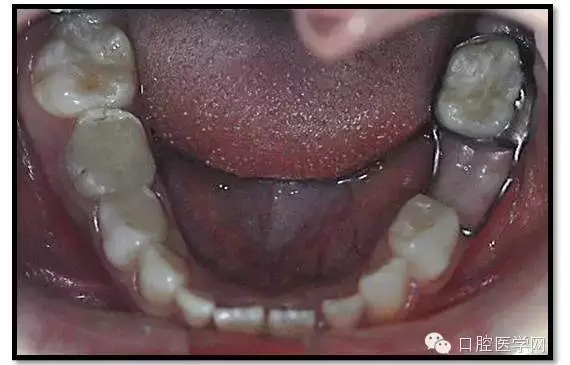

臨床檢查: 75OL齲洞, 舌側(cè)牙體完全劈裂斷端齊齦,探及大量軟化腐質(zhì)。頰側(cè)牙齦紅腫見瘺管,擠壓大量溢膿。叩(±),不松動。X線:75根管空虛,牙根吸收約1/2,根尖周及根分歧大面積透射影,35發(fā)育4期,骨硬板尚連續(xù);51殘根,唇側(cè)牙齦瘺管,叩(±),不松動。X線:51牙根吸收約1/2,根尖周低密度影。

85O、84DO充填體邊緣不密合,叩(±),不松動。84頰側(cè)牙齦略紅腫。X線:84遠(yuǎn)中根及髓室底完全吸收,根分歧透射影,近中根內(nèi)側(cè)見外吸收,44上方骨硬板連續(xù)。85近中根完全吸收,髓室底吸收,根分岐透射影,遠(yuǎn)中根管內(nèi)見根充影像。45發(fā)育4期,骨硬板連續(xù)。

診斷: 75OL、51、85O、84DO慢性根尖炎

65OL、74O中齲 55OL、53DL深齲

16OL、26O、36OB、46OB窩溝淺齲